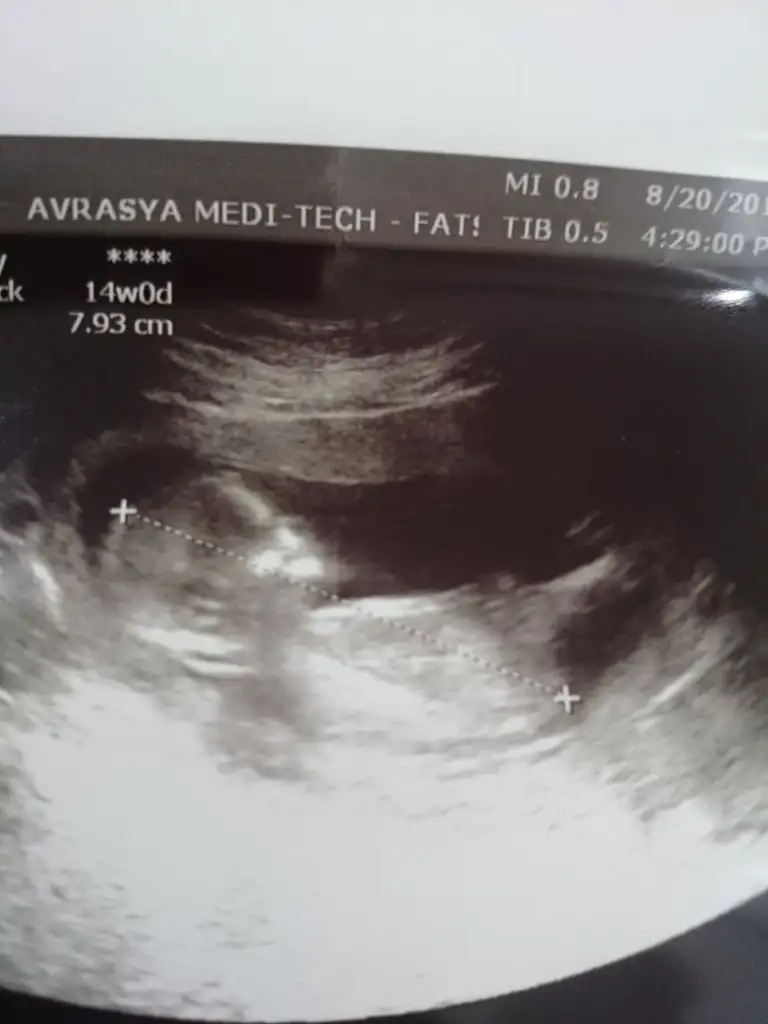

12. Haftanın başıydı 2 li testte daha oluşmadığını söyledi doktorErkeğe benzettim canım.doktor tahminde bulundumu

Bu usg yi hiç çözemedim İnan kiMerhaba bana da tahmin yapabilir misiniz![]()

Bacak arasını göstermedi doktor da tahminde bulundu acıkcası kemik yapısından nasıl oluyorsaKız gibi sanki

Doktor ne tahminde bulundu?Bacak arasını göstermedi doktor da tahminde bulundu acıkcası kemik yapısından nasıl oluyorsahayırlısı

Kemik yapısına göre kız dedi doktorDoktor ne tahminde bulundu?

Ama göremedi bacak arasınıDoktor ne tahminde bulundu?

Kemik yapısına göre kız dedi doktor![]()

Kız bu bebiş,sağlıcakla al kucağına canım.birde erkeğe dönüyormuşAma göremedi bacak arasını![]()